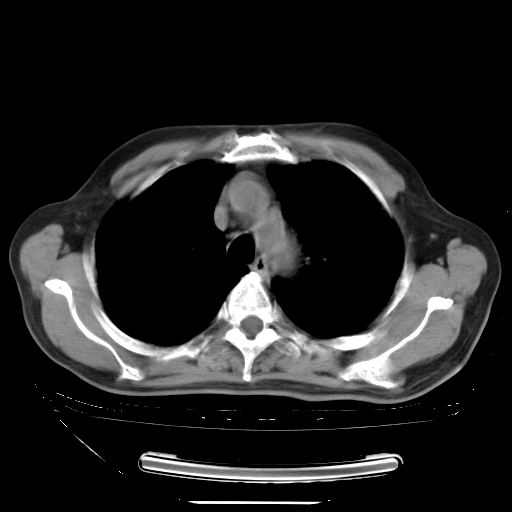

胸腹部CT,诊断意见:左上肺叶钙化灶、左侧胸膜局限性增厚并钙化、胆囊炎。描述部分肺组织呈磨玻璃样改变。